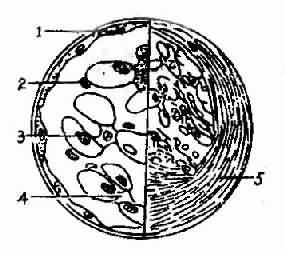

图4-2-3左侧为正常肾小球模式图,右侧为局灶性增殖性肾小球肾炎,部分系膜区系膜细胞和基质增生

1、肾小囊壁层2、基膜3、上皮细胞 4.内皮细胞 5、系膜细胞及基质

图4-2-4 毛细血管内增殖性肾小球肾炎模式图。上皮细胞下电子致密物(免疫复合物)沉积,内皮细胞和系膜细胞增殖,白细胞浸润1.上皮下沉积物2.内皮细胞 3.白细胞 4.系膜细胞